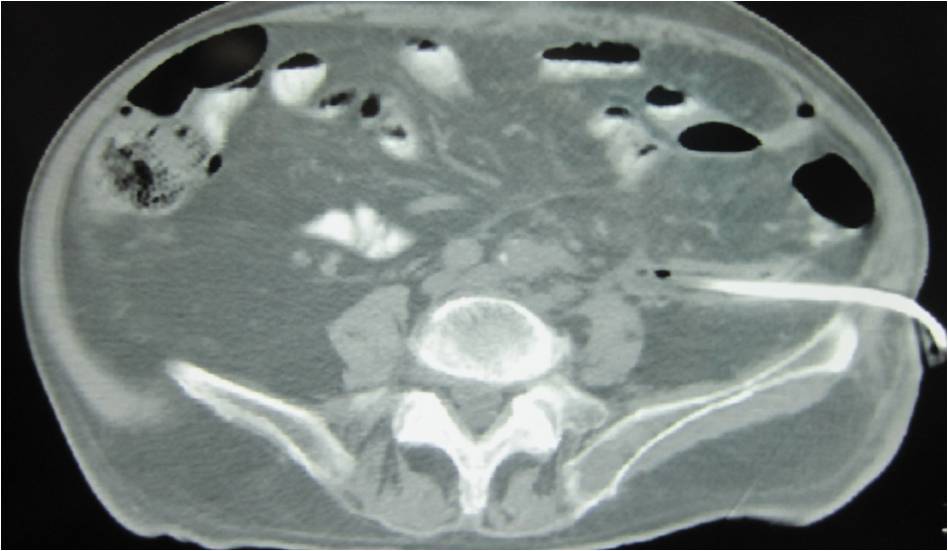

- Paracentisis of an intra-loop abscess

- Successful drainage

- Placement of two sump catheters in a abdominal abscess (surgery of inflammatory bowel disease), displacement of upper one